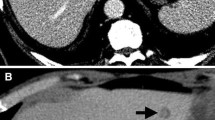

Dynamic contrast-enhanced CT (CECT) involves multi-phase acquisition including true non-contrast, arterial, portal-venous and delayed phase. CRLM are typically hypovascular lesions and appear hypoattenuating compared to normal liver tissue with heterogeneous enhancement on portal venous phase [17]. Since CRLM are hypovascular, arterial phase is typically used for presurgical planning [20]. On delayed images, CRLM can show wash-out contrary to benign pathologies (e.g., hemangiomas) [17]. Newer generation dual-energy CT scanners (DECT), which are becoming mainstream, have further bolstered the role of CT with novel post-processing techniques that improve lesion conspicuity by enhancing the liver-to-lesion contrast [21, 22] (Fig. 5.1).

Dual-Energy CT to improve lesion conspicuity. An 85-year-old male with multiple CRLM. Post-contrast axial reconstructions of material density-iodine in gray scale (a) and color-overlay (b) show better conspicuity of a hepatic lesion (arrows), which is hard to visualize on conventional single-energy CT image (c)